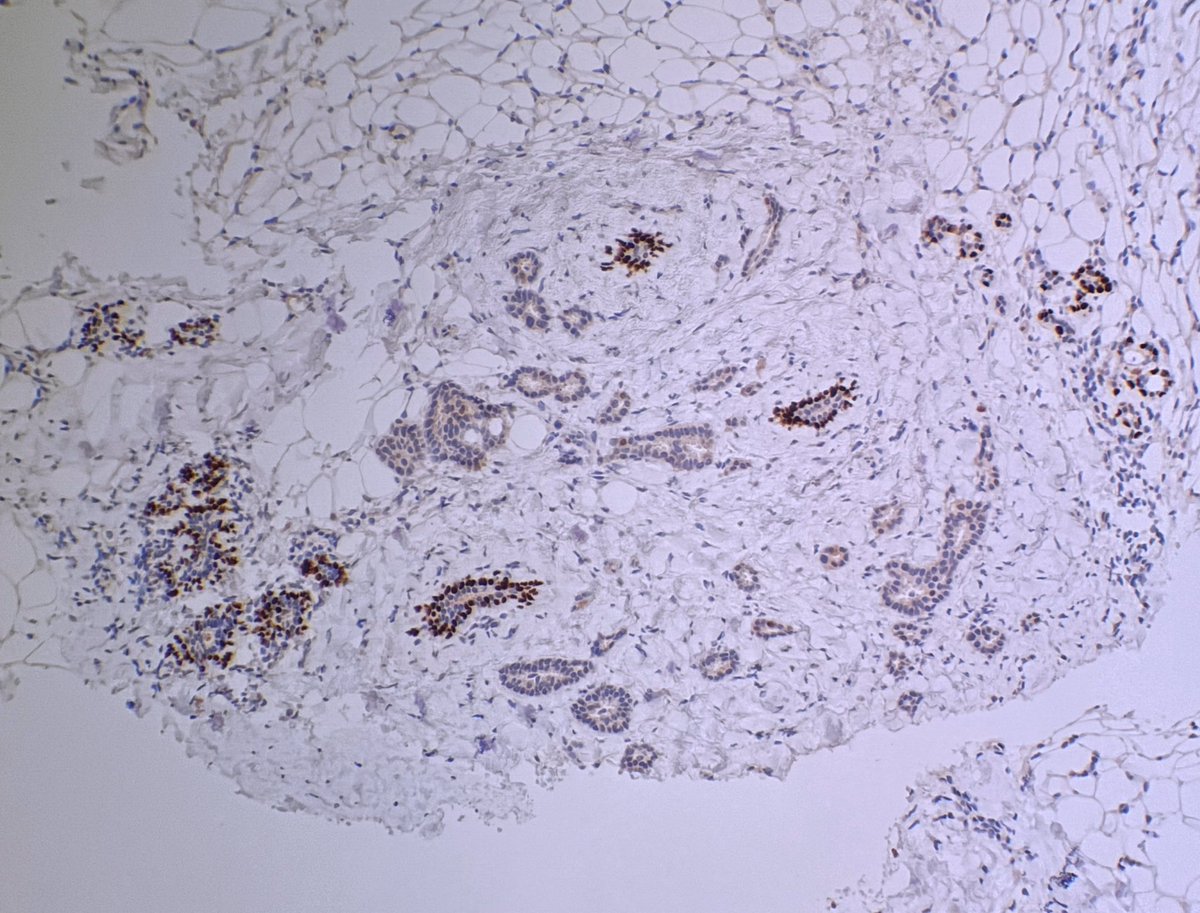

1/ Thanks everyone ๐Ÿ™๐Ÿ™๐Ÿ™ great answers ๐Ÿ‘๐Ÿ‘ you are all too good!!!! Indeed this is MGA- microglandular adenosis, that today is considered a non-obligate precursor of some triple โ€“negative breast carcinomas.

Indeed this is MGA- microglandular adenosis, that today is considered a non-obligate precursor of some triple โ€“negative breast carcinomas.